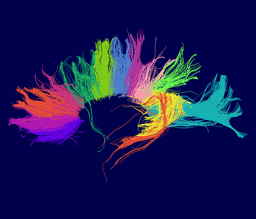

We are developing tools in the 3D Slicer for automatic clustering of tractographic paths through diffusion tensor MRI (DTI) data. By grouping tractographic paths based on shape and location, the white matter architecture may be more clearly visualized, and interesting properties of the clusters (such as for example FA or Westin's linear measure) may be quantified.

Our implementation uses spectral clustering, a method for grouping data using eigenvectors of a data affinity matrix. This image gives an overview of the method. On the left example input tractographic paths are shown (these were created by manually seeding in the 3D Slicer). The center image shows an embedding of the tracts as points in 2D, where the distance between points is related to their shape similarity. This embedding was calculated as an intermediate step during spectral clustering. The image on the right shows the final output in the 3D Slicer, where tractographic paths are colored by cluster membership.